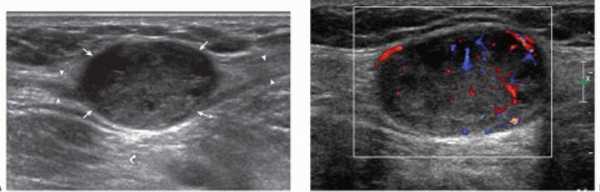

На снимке образование, подозрительное на фибросаркому. При допплерографии (справа) определяется кровоток в сосудах, питающих опухоль